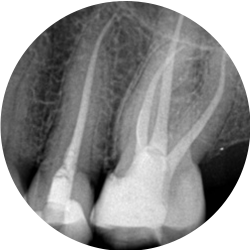

Endodontics is the branch of dentistry which is concerned with the morphology, physiology and pathology of the human dental pulp and periradicular tissues. Its study and practice encompass the basic clinical sciences including biology of the normal pulp; the etiology, diagnosis, prevention, and treatment of diseases and injuries of the pulp and associated periradicular conditions.

Bacteria associated with decay, deep restorations, fractures, trauma or periodontal disease may irreversibly damage the pulp. In order to preserve a tooth, in which this has occurred, it is necessary to remove the injured, infected tissue. This procedure is known as root canal therapy.